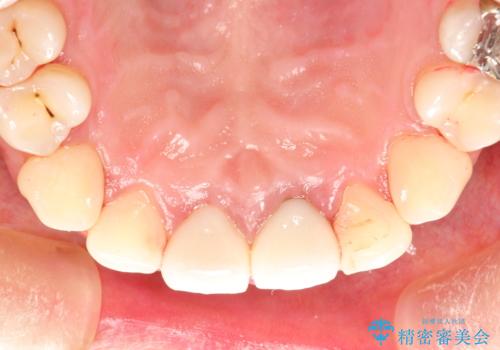

終了時

かなり久しぶりの歯科医院との事で、全体的に古くからの歯垢・歯石が多く付着していたため、自費クリーニング(PMTC)60分コース・歯周ポケット検査(保険適応)を行いました。